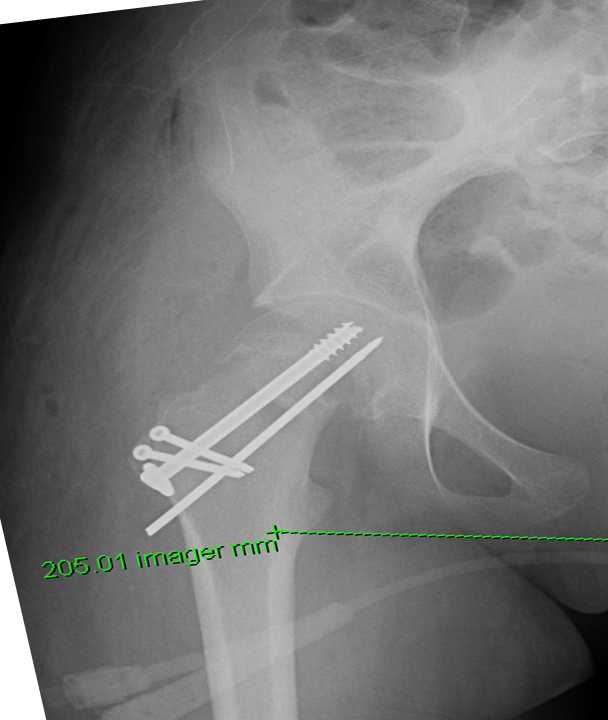

Femoral neck osteotomy with complete correction of the slip

Femoral neck osteotomy with complete correction of the slip.